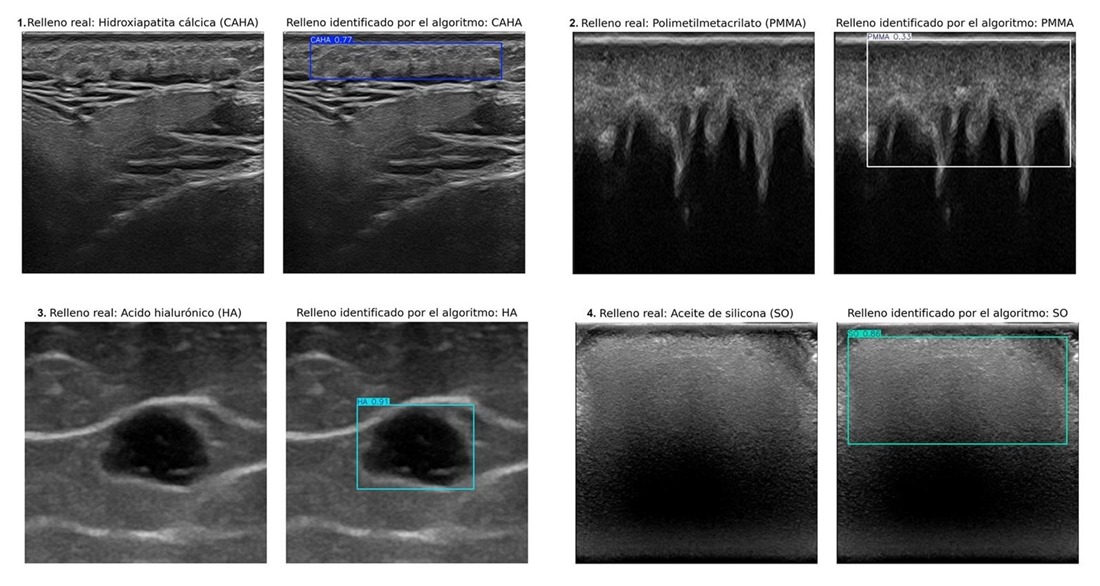

Un equipo internacional de investigadores de las universidades de Granada y Chile ha desarrollado un sistema de inteligencia artificial (IA) capaz de identificar automáticamente cuatro tipos de rellenos estéticos mediante imágenes ecográficas. Publicado en la revista Journal of Ultrasound in Medicine, este avance permitirá acelerar el diagnóstico de complicaciones, optimizar la planificación de tratamientos y reducir la dependencia de especialistas altamente cualificados.

La ecografía, aunque es el método más eficaz para detectar estos rellenos, requiere una amplia experiencia clínica para interpretar las imágenes. La IA desarrollada por la doctora Ximena Worstman de la Universidad de Chile y los profesores Manuel Lozano y Francisco J. Rodríguez de la Universidad de Granada integra aprendizaje profundo para identificar rellenos de hidroxiapatita cálcica, ácido hialurónico, polimetilmetacrilato y aceite de silicona.

El sistema se ha entrenado con equipos ecográficos de diversa complejidad, desde portátiles hasta dispositivos de alta gama, para garantizar su adaptabilidad en distintos entornos clínicos. Este desarrollo representa un paso importante hacia una medicina estética más precisa, accesible e innovadora, atendiendo un problema clínico creciente en la era de la belleza inyectable.